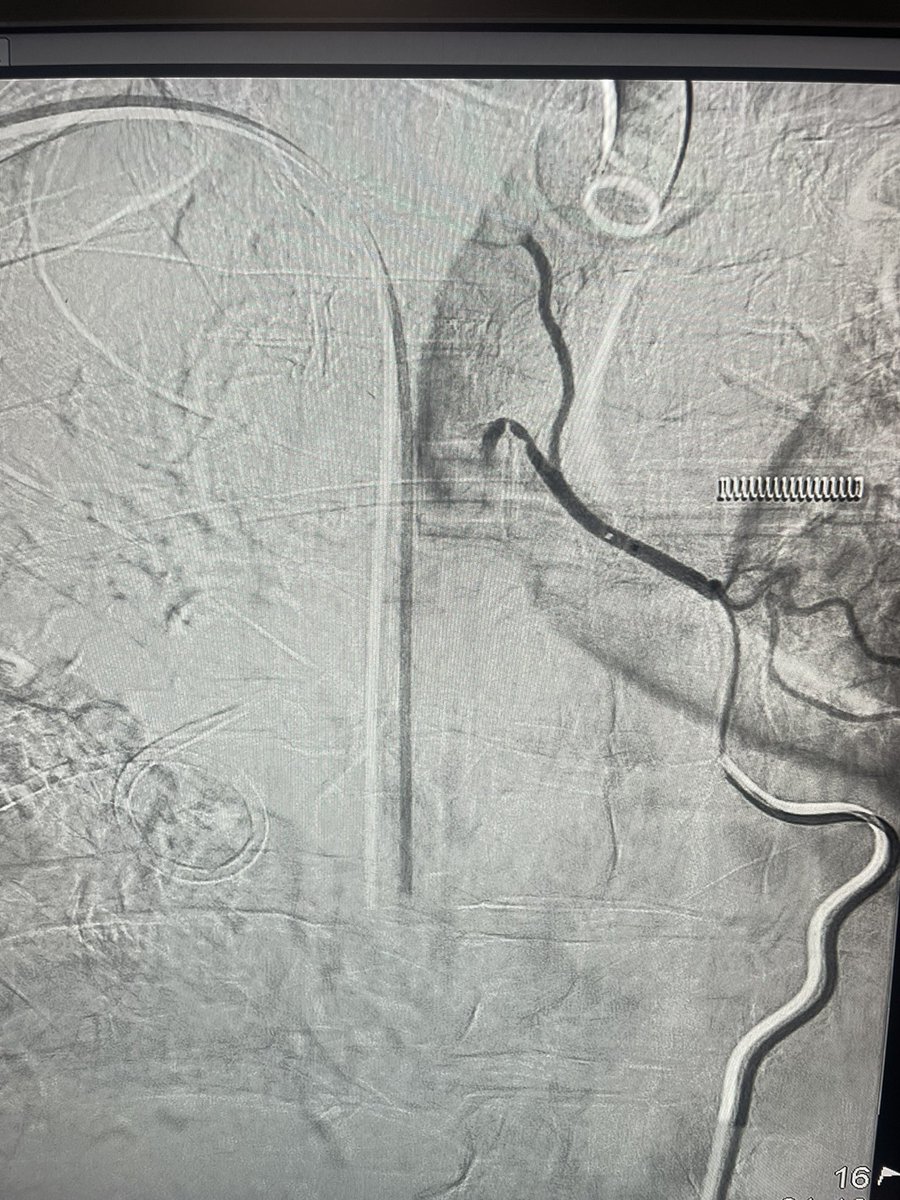

37 year old man, k/c neurofibromatosis type 1 with right renal artery stenosis and resistant hypertension. Balloon angioplasty was performed and nothing left behind.